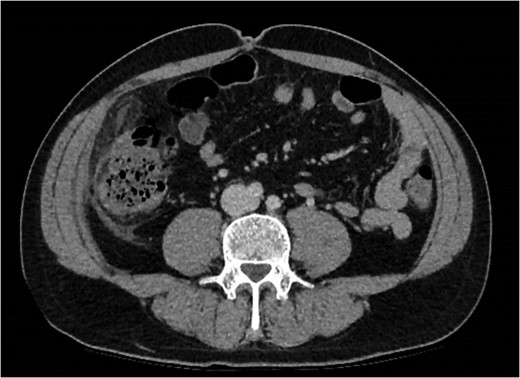

An initial differential diagnosis was made as cholecystitis. Appropriate intravenous antibiotics were commenced. An abdominal ultrasound demonstrated a thin-walled gallbladder without gallstones and a normal common bile duct caliber. There was however a trace of free fluid in the right iliac fossa. The sonographer was unable to identify a normal appendix. The following afternoon a CT scan of his abdomen and pelvis demonstrated fluid in the right iliac fossa as well as his rectovesicular pouch. The appendix was normal, but there was tissue stranding adjacent to the caecum and ascending colon to the tip of the liver (Figs 1 and 2).

Abdominal CT demonstrating soft tissue stranding and odema inferior to a normal gallbladder, extending to the caecum.